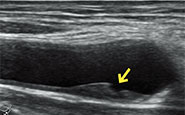

②頚動脈超音波検査(頚動脈エコー)

脳に血液を送り込む頚動脈(首の血管)の動脈硬化(血管の硬さ)の程度や血管壁の損傷により血栓ができていないか、血管が狭くなっていないか、などを調べます。頚動脈の動脈硬化によって血管が狭くなったり血管壁が厚くなったりしている場合、脳卒中の原因になります。また、頚動脈の動脈硬化の状態は全身の動脈硬化の指標の一つとして考えられています。